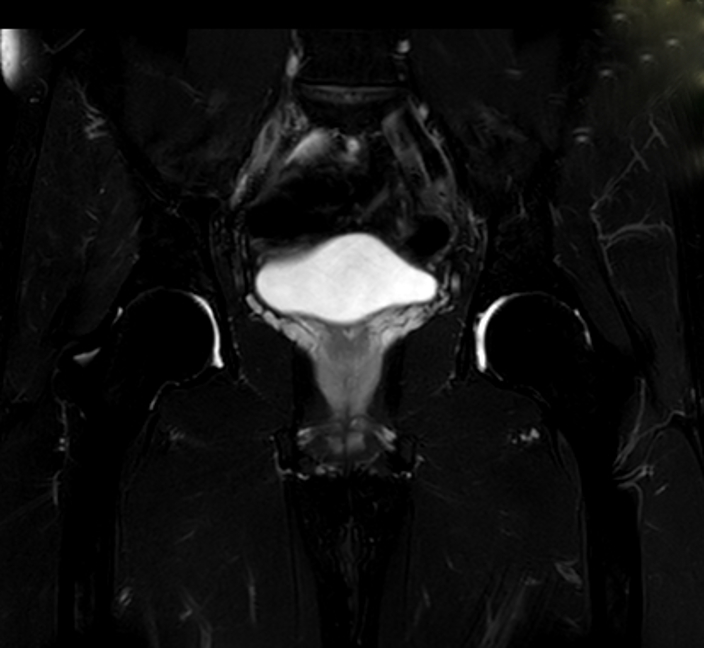

Hüfte, Becken und Beckenboden sowie die sich dort befindlichen Organe lassen sich mit einer MRT in hoher Auflösung darstellen. Bei manchen Untersuchungen muss jedoch ein Kontrastmittel angewendet werden, das in seltenen Fällen zu allergischen Reaktionen führen kann. MRT-Becken-Untersuchung mit freiem Blick aus dem System .Die Kernspintomographie ist daher ein ebenso zuverlässiges wie schonendes bildgebendes Verfahren, das sehr präzise Aussagen zu vielen Fragestellungen zum Beispiel im Bereich der Wirbelsäule ermöglicht.Nun erfolgen die Auswertung der Bilder und die Erstellung eines schriftlichen Befundberichts durch die Radiologie des Röntgeninstituts. Anhand dieser Bilder kann der Arzt Organstrukturen und -funktionen beurteilen. Sie basiert auf starken Magnetfeldern und hochfrequenten Radiowellen und erzeugt Bilder in allerhöchster Präzision.

Dieser querschnittliche Atlas der menschlichen Anatomie der unteren Gliedmaßen ist ein interaktives Hilfsmittel, das auf MRT-Achsenaufnahmen des menschlichen Beins basiert. Bei der MRT der . Hierbei ist nicht nur der knöcherne Teil des Beckens zu sehen, sondern auch Gelenke und insbesondere Organe, die sich im Beckenbereich befinden. Zur Magnetresonanztomographie des Beins zählen Aufnahmen von Hüfte, Oberschenkel, Knie und Unterschenkel. Für Ihren Arzt sind MRT Bilder ein wichtiges Kriterium für die weitere Therapie.

MRT Becken